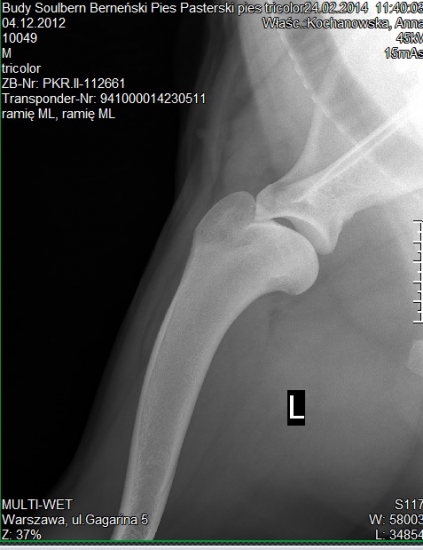

W dniu dzisiejszym BUDY Soulbern czyli Balus jako pierwszy z rodzeństwa przeszedł pozytywnie, komplet prześwietleń pod kątem dysplazji stawów biodrowych, łokciowych i OCD stawów barkowych .

Balus jest wolny od dysplazji z wynikiem HD B, ED 0/0, OCD neg. :-D

bark lewy

bark prawy